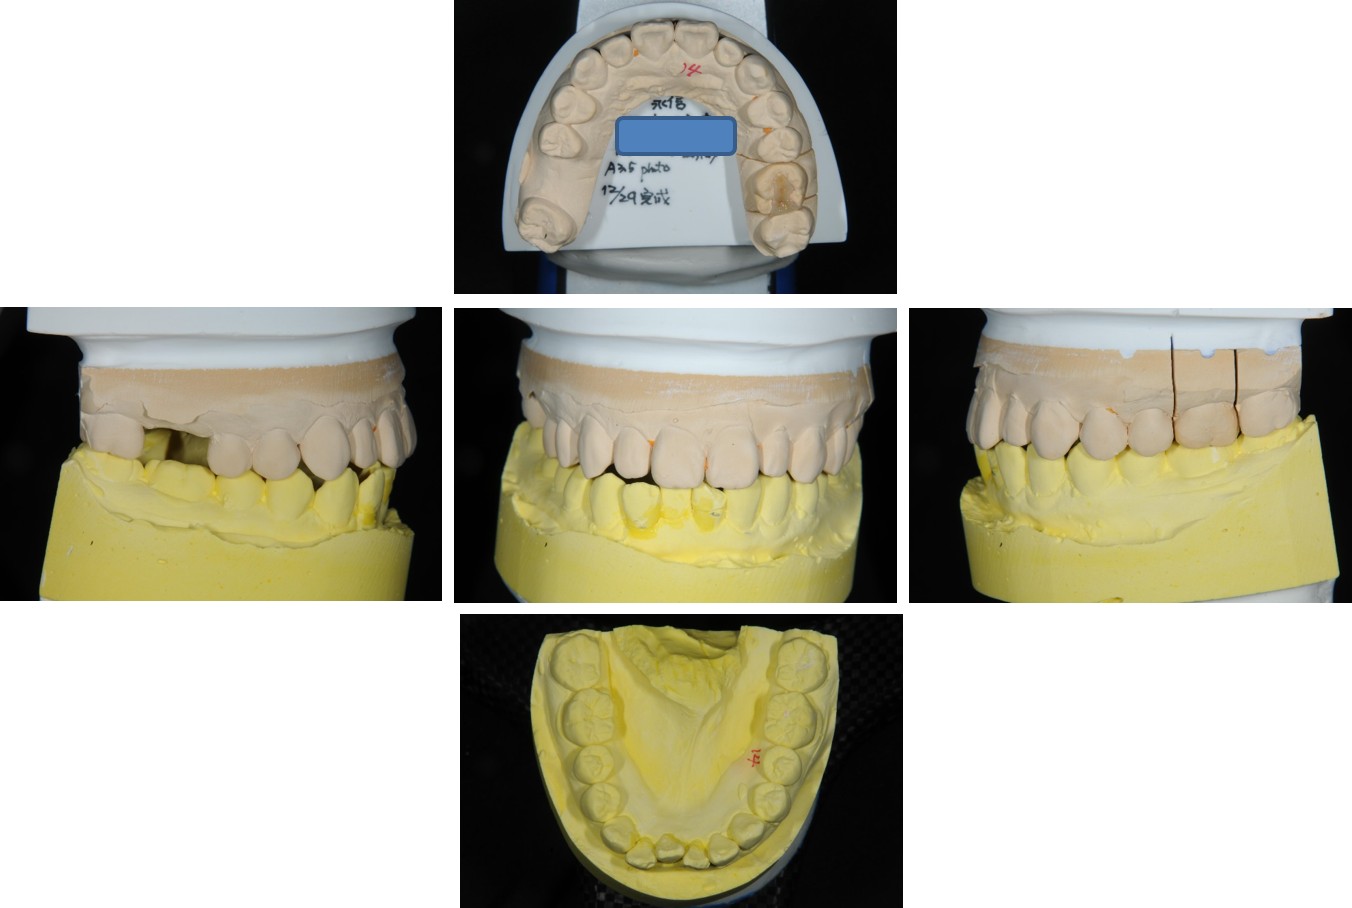

經面弓轉移,上咬合器

技師於咬合器上製作模型